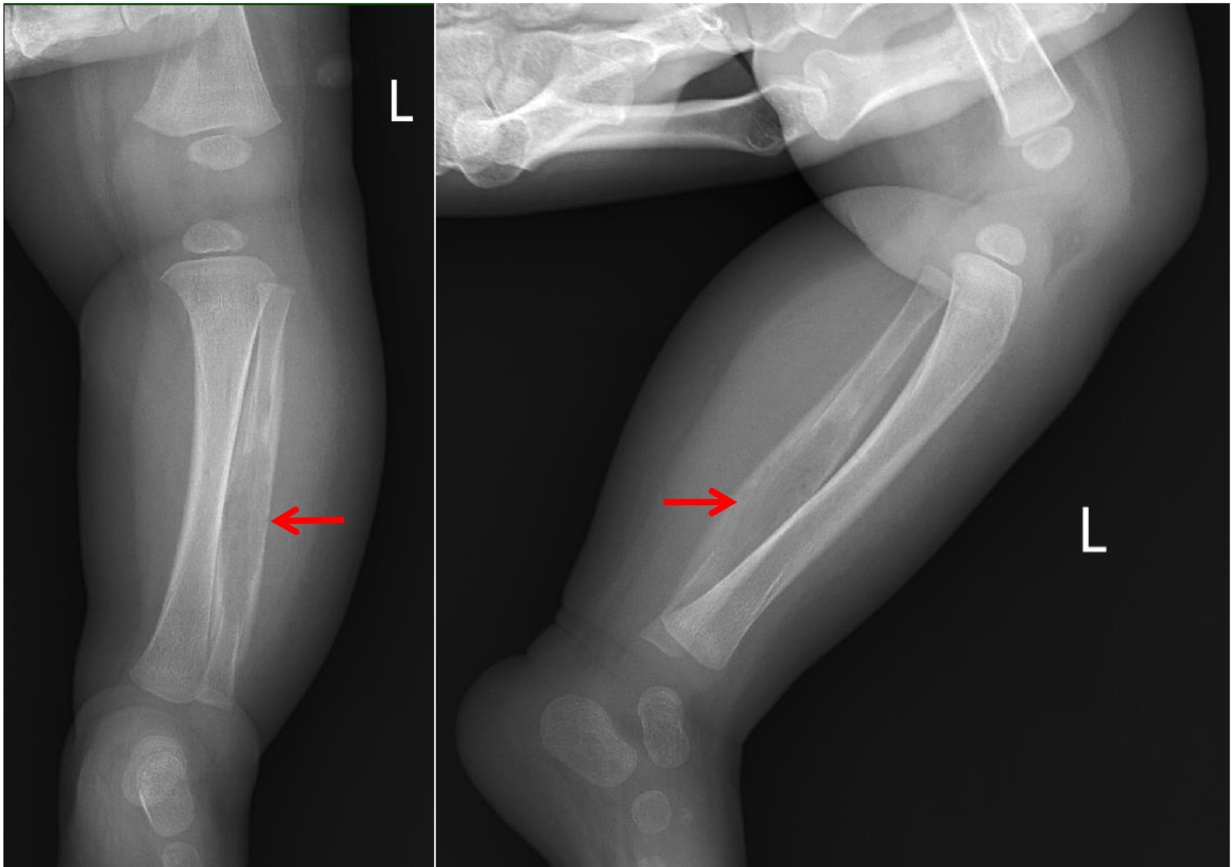

(5) 入院后完善相关检查:2025-09-10,CRP+血常规:C反应蛋白21.43 (mg/L)↑,白细胞计数13.24 (×10^9/L),中性粒细胞计数4.62 (×10^9/L),淋巴细胞计数7.39 (×10^9/L),红细胞计数3.96 (×10^12/L),血红蛋白95 (g/L)↓,血小板计数546 (×10^9/L);2025-09-22,CRP+血常规:C反应蛋白43.80 (mg/L)↑,白细胞计数11.24 (×10^9/L),中性粒细胞计数4.17 (×10^9/L),淋巴细胞计数6.23 (×10^9/L),红细胞计数3.56 (×10^12/L),血红蛋白82 (g/L)↓,血小板计数627 (×10^9/L)↑;2025-09-17,细胞因子:白介素6 29.66 (pg/ml)↑,白介素102.62 (pg/ml)↑,干扰素γ 23.76 (pg/ml)↑;2025-09-23,红细胞沉降率76 (mm/h)↑;大小便常规、降钙素原无异常;肝肾功能、电解质、血糖、血脂、心肌酶谱、凝血功能、免疫功能、风湿全套、狼疮全套大致正常,贫血三项:铁蛋白244.06 (ng/mL)↑;病原学检查:尿培养、痰涂片、输血前、血培养、未见异常。2025-09-16,病原体高通量测序基因检测:人类疱疹病毒5型(CMV)序列数(1993)相对丰度(86.5%);2025-09-10上呼吸道六项病原核酸检测:入院时阴性,住院期间(2025-09-16)呼吸道合胞病毒,阳性(+)↑。影像学检查:2025-09-12,左胫腓骨磁共振(如图2):左侧腓骨髓腔长段囊腔样扩展,髓腔内可见异常强化,骨皮质菲薄,骨膜层状反应性环状增生增厚,骨质破坏不明显,周围软组织明显肿胀、无脓肿及坏死灶形成。2025-09-17,胸部正位片(如图3) + 右股骨正位片和右胫腓骨正位片(如图4):右肩胛骨重叠区、右股骨远端、右胫骨上段低密度影,性质待定,建议进一步检查。2025-09-23,颌面部磁共振(如图5):下颌骨左侧部骨皮质明显不规则增厚,边缘模糊、毛糙,呈T1W1、T2W1低信号,临近软组织肿胀呈明显T2W1高信号。腹部超声未见异常。病理检查:2025-09-15,免疫组化:(左侧小腿软组织)送检肌组织,肌间可见少许淋巴细胞、嗜酸性粒细胞及中性粒细胞浸润,多切片未见恶性证据,请结合临床综合考虑。免疫组化IHC: A01: CK (pan) (−),CD207 (−),CD20 (少量B细胞+),CD1a (−),S-100 (−),Ki67 (+, 约10%),CD3 (少量T细胞+),TdT (−),CD34 (血管+),MPO (少量+),SMA (−)。原位杂交:EBER (−)。基因检查:GATA2 (chr3: 128200145)杂合变异;EXT2 (chr11: 44219362)杂合变异。

Figure 2. MRI Findings of the left tibia and fibula (Left: pre-contrast; Right: post-contrast)

2. 左侧胫腓骨磁共振(左图:平扫,右图:增强)

左侧腓骨髓腔长段囊腔样扩张,髓腔内可见异常强化、无脓肿形成,骨皮质菲薄,骨膜层状反应性环状增生增厚,骨质破坏不明显,周围软组织明显肿胀、无脓肿及坏死灶形成。①、④、⑥为骨膜层状反应性环状增生增厚;②、⑦为扩张的骨髓腔,腔内未见脓肿;③、⑤可见哈弗氏管的骨皮质扩大,周围未见脓肿。